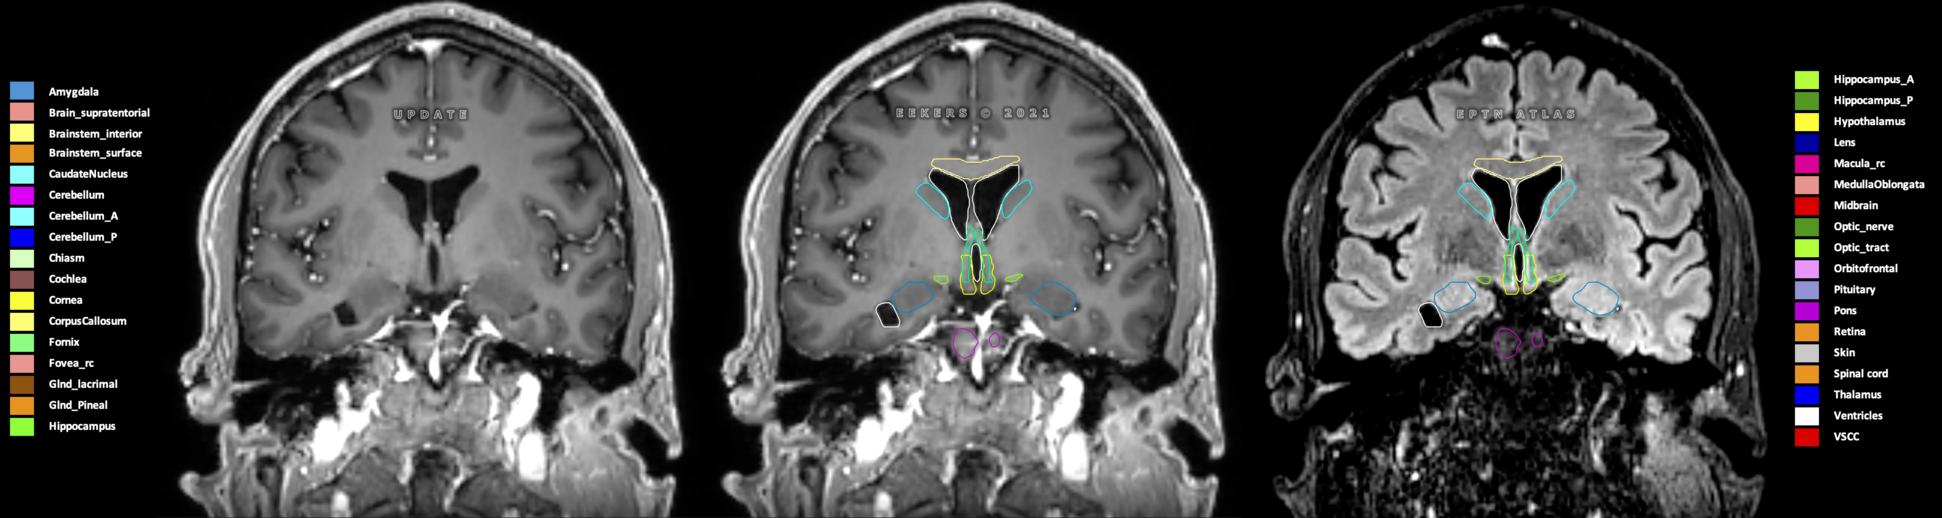

Eekers et al. have published an international neurological atlas for contouring of organs at risk in consensus with the European Particle Therapy Network (EPTN) in 2018 and an update in 2021. The purpose of this consensus atlas is to decrease inter- and intra-observer variability in delineating OARs relevant for neuro-oncology.

Included are all OARs known to be relevant for radiation-induced toxicity in neuro-oncology: brain, brainstem (midbrain, pons, medulla oblongata), chiasm, cerebellum (anterior & posterior), cochlea, cornea, hippocampus (anterior & posterior), hypothalamus, lens, lacrimal gland, optic nerve, pituitary, skin, and vestibular & semicircular canals. To further facilitate research on cognition, vision and radiological changes after irradiation of the brain, potential clinically-relevant OARs are included: amygdala, caudate nucleus, cerebellum (anterior & posterior), corpus callosum, fornix, macula, optic tract, orbitofrontal cortex, periventricular space (PVS), pineal gland, and thalamus.

Three-dimensional delineation of the 25 consensus OARs for neuro-oncology are shown on CT (WW/WL 120/40, 3000/600), 3T MR images, (T1Gd, T2FLAIR 1mm) and 7T MR (MP2RAGE 0.7 mm). All are presented in transversal, sagittal and coronal view.